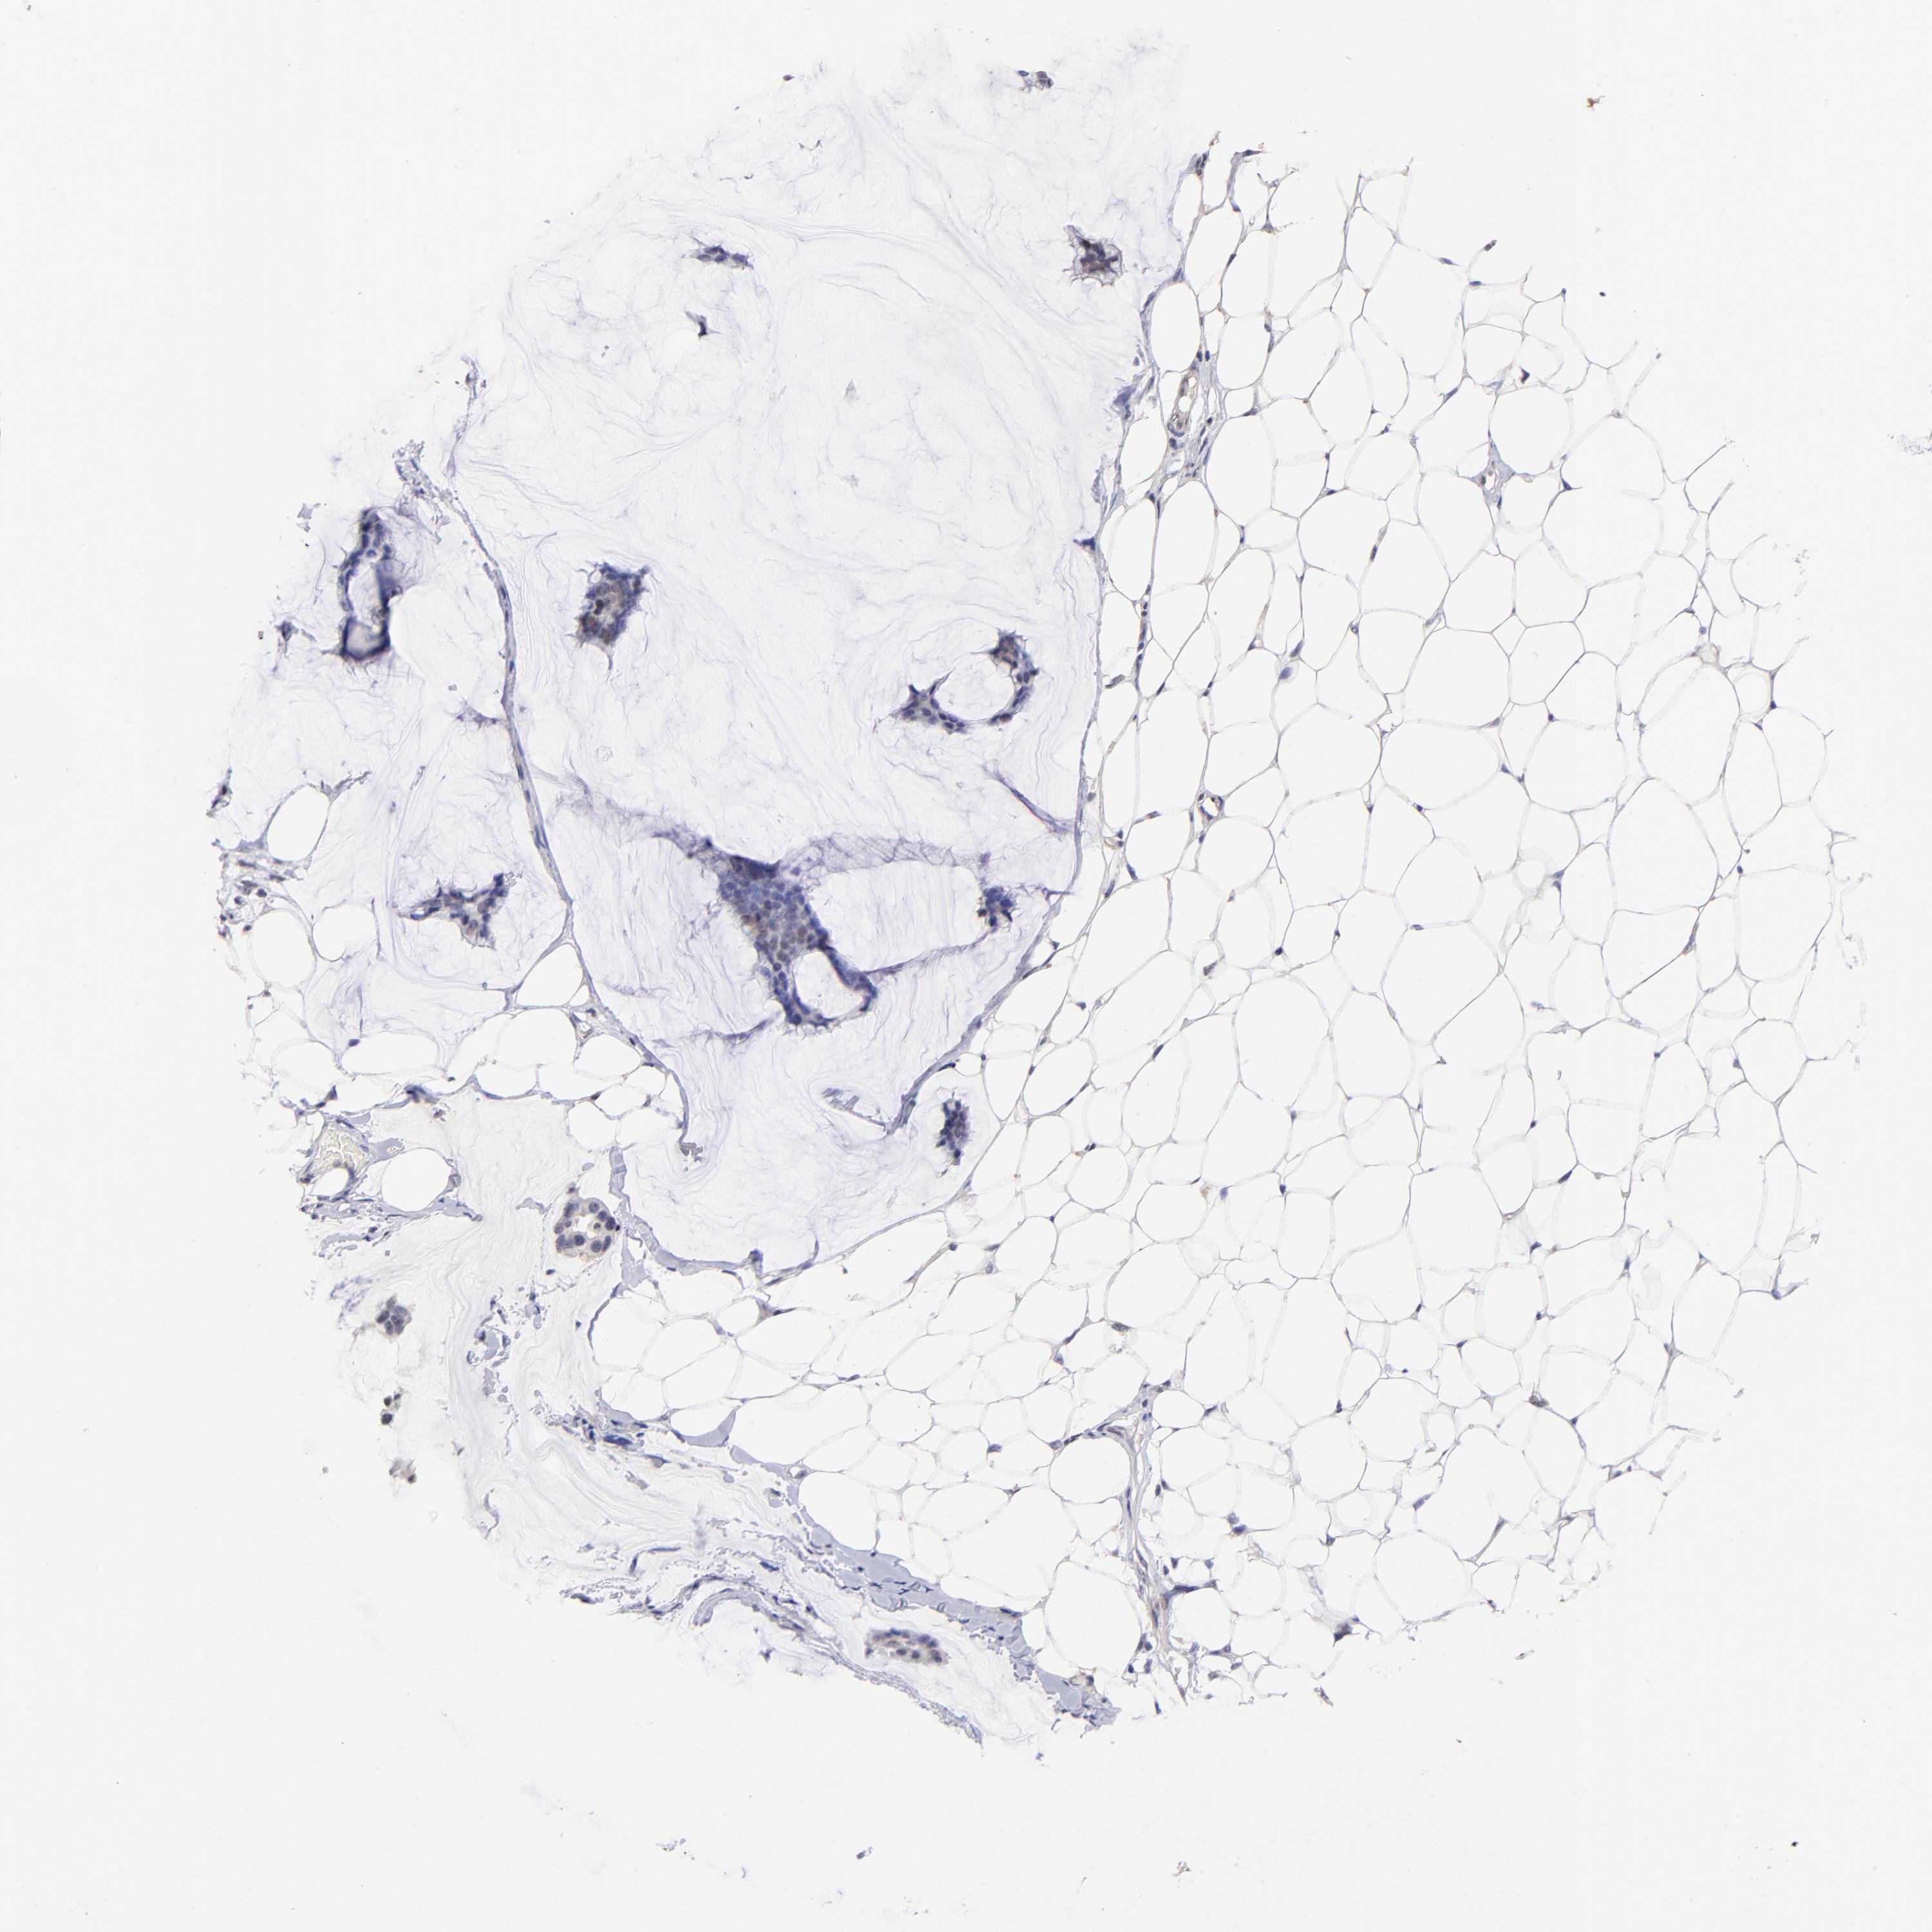

BRCA TCGA BRCA VALIDATION PROTEIN EXPRESSION